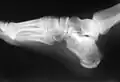

Raio-X de uma fratura de calcâneo